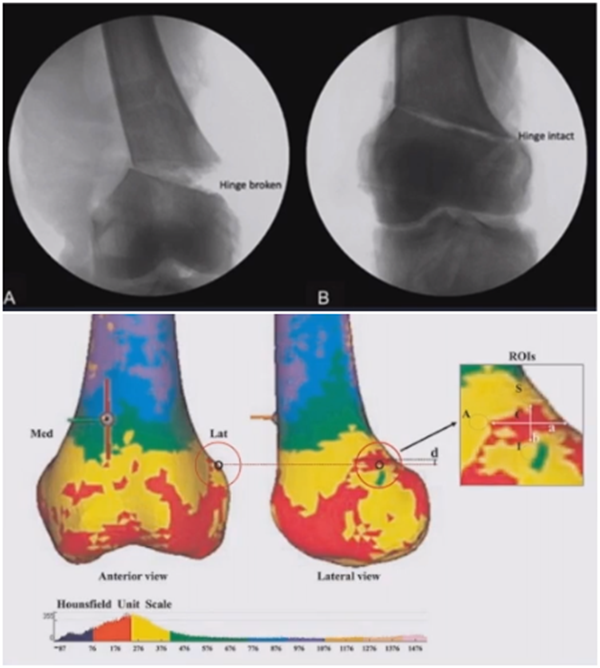

2、并发症

术中常见矫正不足或过度矫正、合页骨折、血管损伤等。术后常见力线矫正丢失、不愈合或延迟愈合等。此处重点讲解术中合页骨折和术后力线丢失两种并发症。

(1)合页骨折

对于术中出现的合页骨折,此时还有一定的稳定性,可以调整力线固定以后,由前外向后内打一根防旋螺钉,这样仍然是比较稳定,术后康复计划与正常一样。

对于术中合页骨折,但非常不稳定、无法控制力线的情况,可以由外侧向股骨外髁打入一枚2.0的克氏针,因为克氏针具有一定弹性,相当于重建合页临时稳定性,在此基础上再去调整力线,做固定。

晚期出现的合页骨折,此时力线已经改变,只能进行翻修。

(2)术后力线丢失

对于力线丢失原则是重新矫正力线,重新固定,通常在合页端加上内固定物,主要目的是为了抗旋,有一些截骨端还需要进行植骨。术后早活动晚负重。

病例,X患者,女,双侧外翻膝,行双侧DFO。

术后6周摔伤,一侧出现膝内翻。

影像学检查显示左侧出现合页断裂。

进行翻修,术前力线显示内翻。

术中发现螺钉松动,截骨端出现坎插迹象。

近端螺钉松开,调整力线,重新固定后,在外侧加小钢板抗旋。

术后10周复查,力线较好。